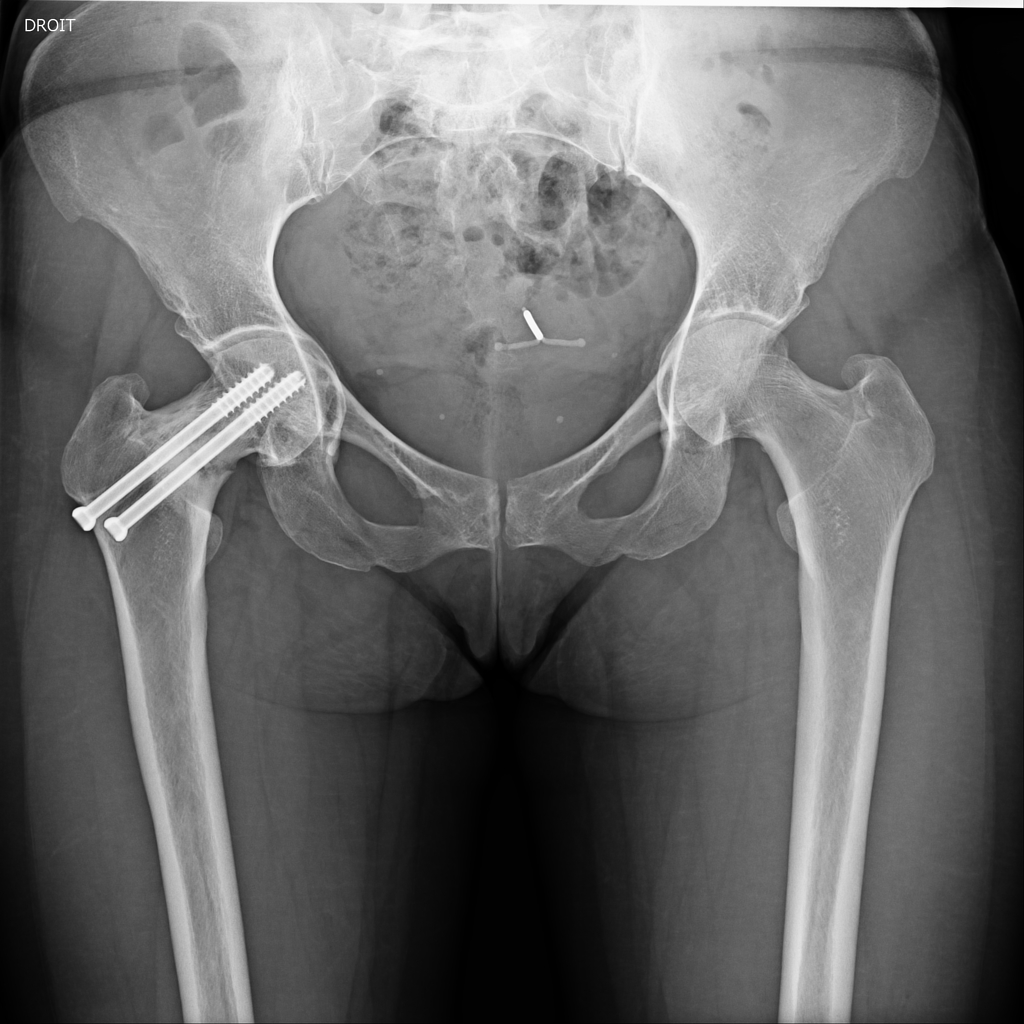

Femoral Neck Fractures Trauma Orthobullets Surgery Femoral Neck Fracture Surgeons may recommend a full or partial hip replacement if the blood supply to the ball part of the hip joint was damaged during. How is a femoral neck fracture treated? The garden classification of femoral neck fractures (fnf) dictates treatment via internal fixation or hip replacement, including. Neck of femur fractures are typically caused either by low energy injuries. Surgery Femoral Neck Fracture.

How is a femoral neck fracture treated? The garden classification of femoral neck fractures (fnf) dictates treatment via internal fixation or hip replacement, including. Surgeons may recommend a full or partial hip replacement if the blood supply to the ball part of the hip joint was damaged during. Surgery is the most common treatment for a femoral neck fracture, though. Neck of femur fractures are typically caused either by low energy injuries (the most common type), such as a fall in frail older patient, or high energy injuries, such as a road. Should consider using the anterolateral approach and selective use of larger heads in the setting of a femoral neck fracture advantages improved functional hip scores and lower.